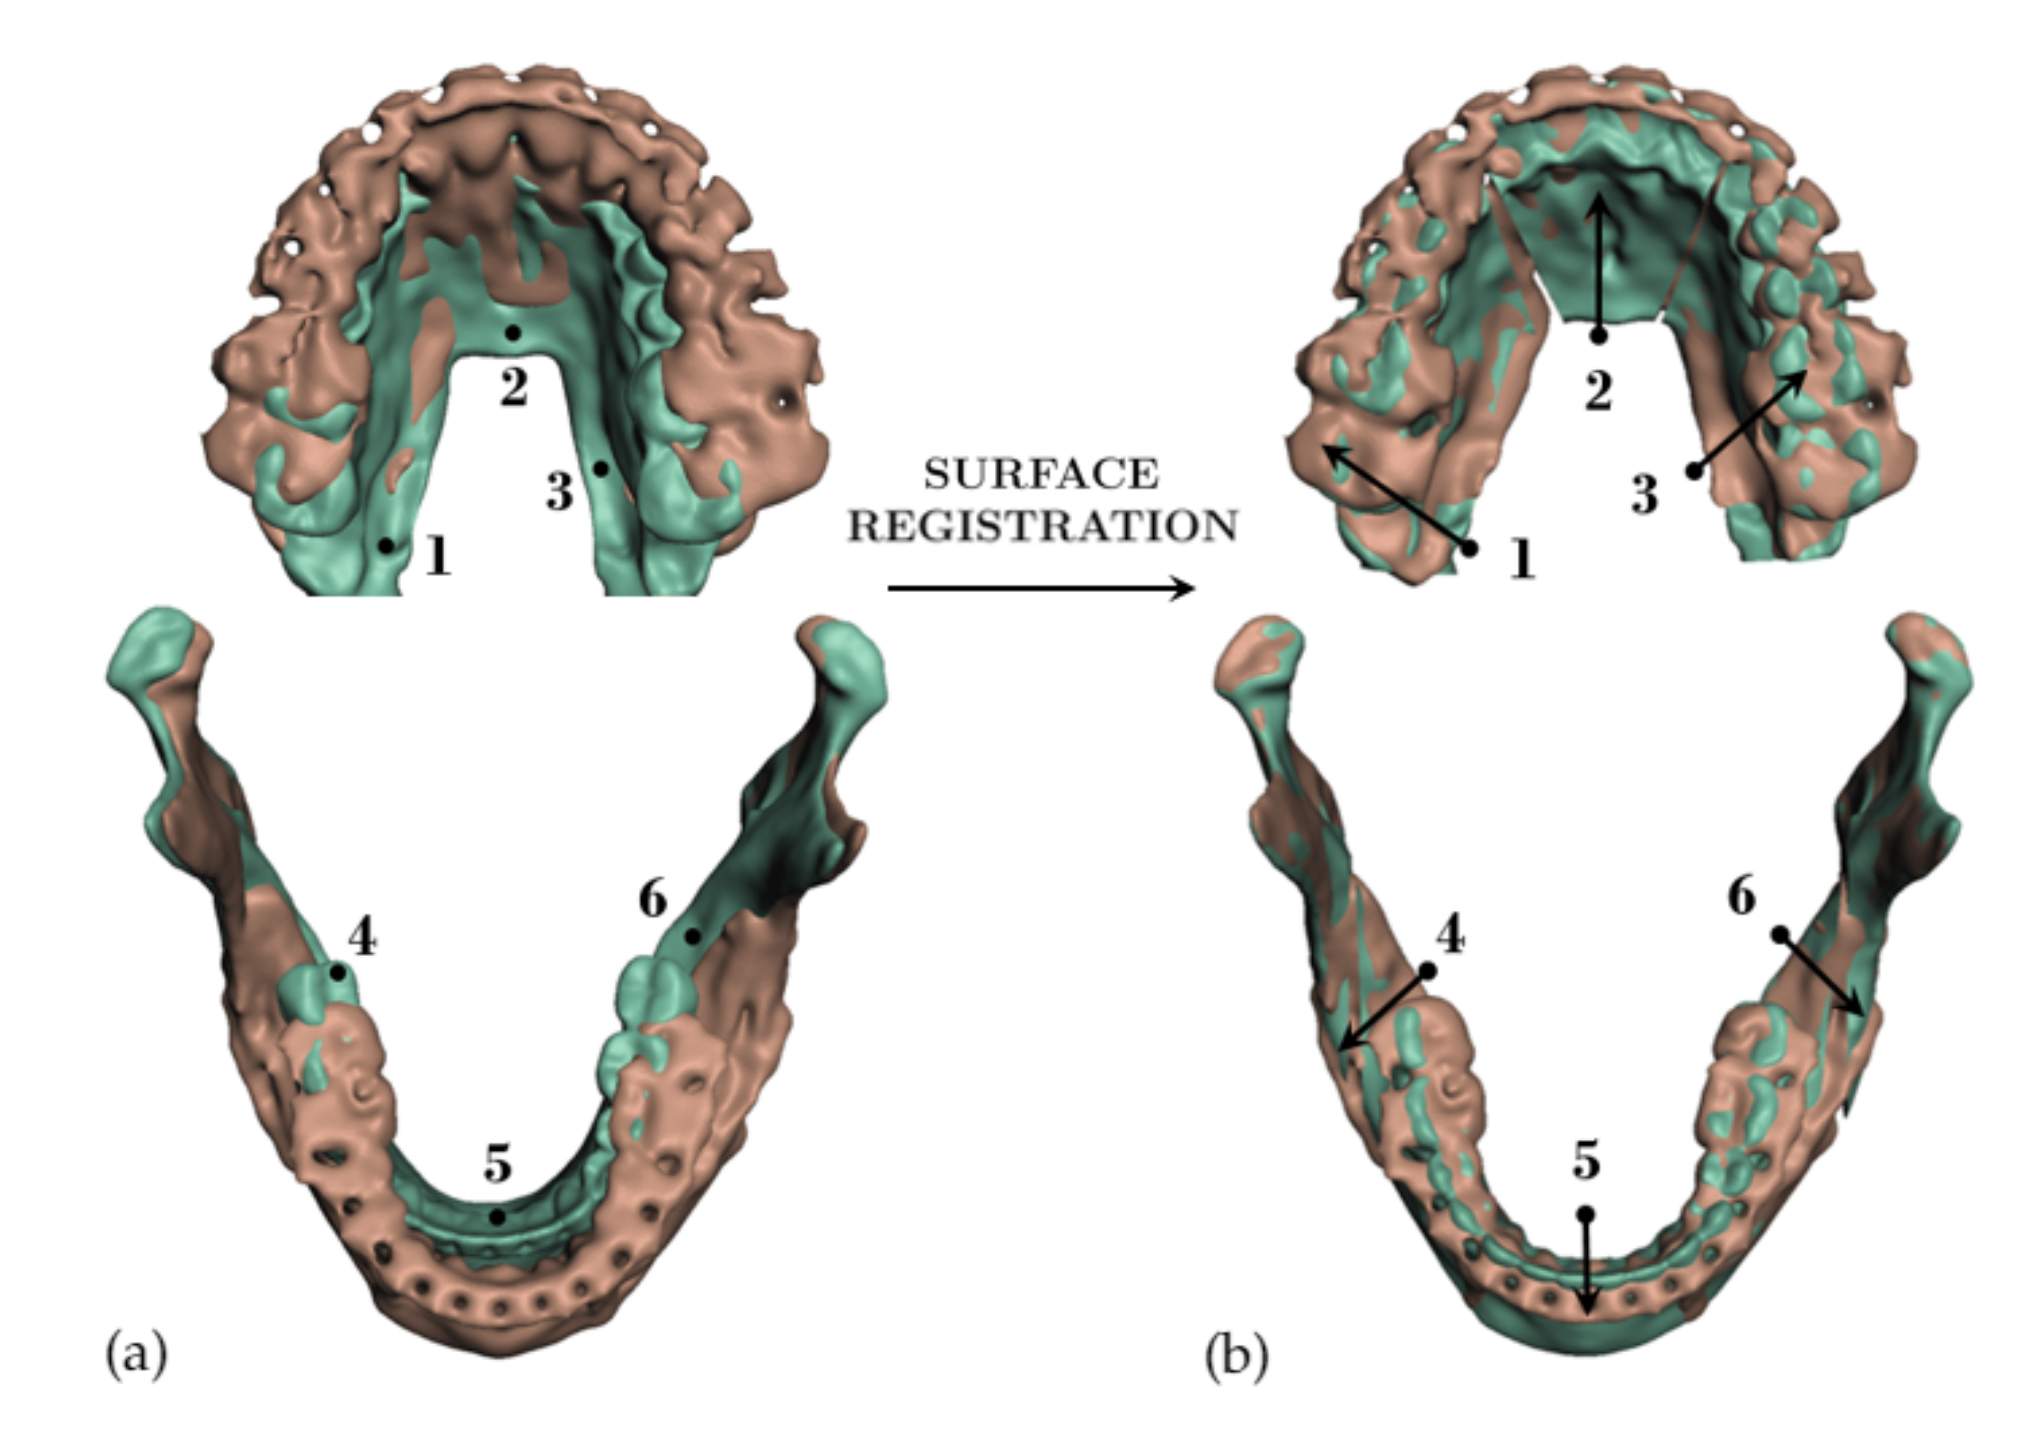

3.1. Validation Methodology

3.2. Test Cases

3.3. Simulation Error and Performance

- Segmentation of the maxilla and mandible. For all patients, the highest error (except for the neck, which is not clinically relevant as discussed above) appears near the cut areas, both of the maxilla (e.g., patients M5 and M7) and the mandible (e.g., patients M1 and M3). This is probably due to the presence of fixation plates and/or bone grafts in the real result (e.g., patient M10, whose maxilla was not segmented, but where the presence of bone graft has been confirmed by the surgeon who carried out the intervention). As a consequence, patients with a segmented maxilla and/or mandible show in general larger error than those without segmented bones. However, the smooth coupling method proposed in Section 2.3.3 reduces considerably the error in cut areas, as shown in Figure 2.